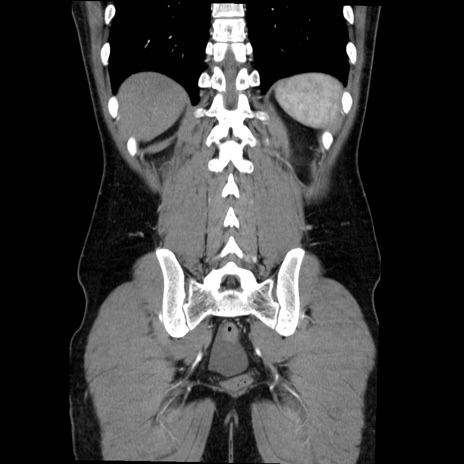

症例36(冠状断像)

【症例】20歳代 男性

【主訴】心窩部痛

【現病歴】今朝より上腹部痛あり。一旦軽快していたが再度出現したため救急要請。昨日夕に白身の魚を含む刺身を食べた。

【身体所見】BP 136/89mmHg、HR 74/min、BT 37.0℃、腹部:膨満、軟、心窩部に圧痛あり。反跳痛なし、筋性防御なし、腸雑音やや亢進あり。

【データ】WBC 17700、CRP 0.48